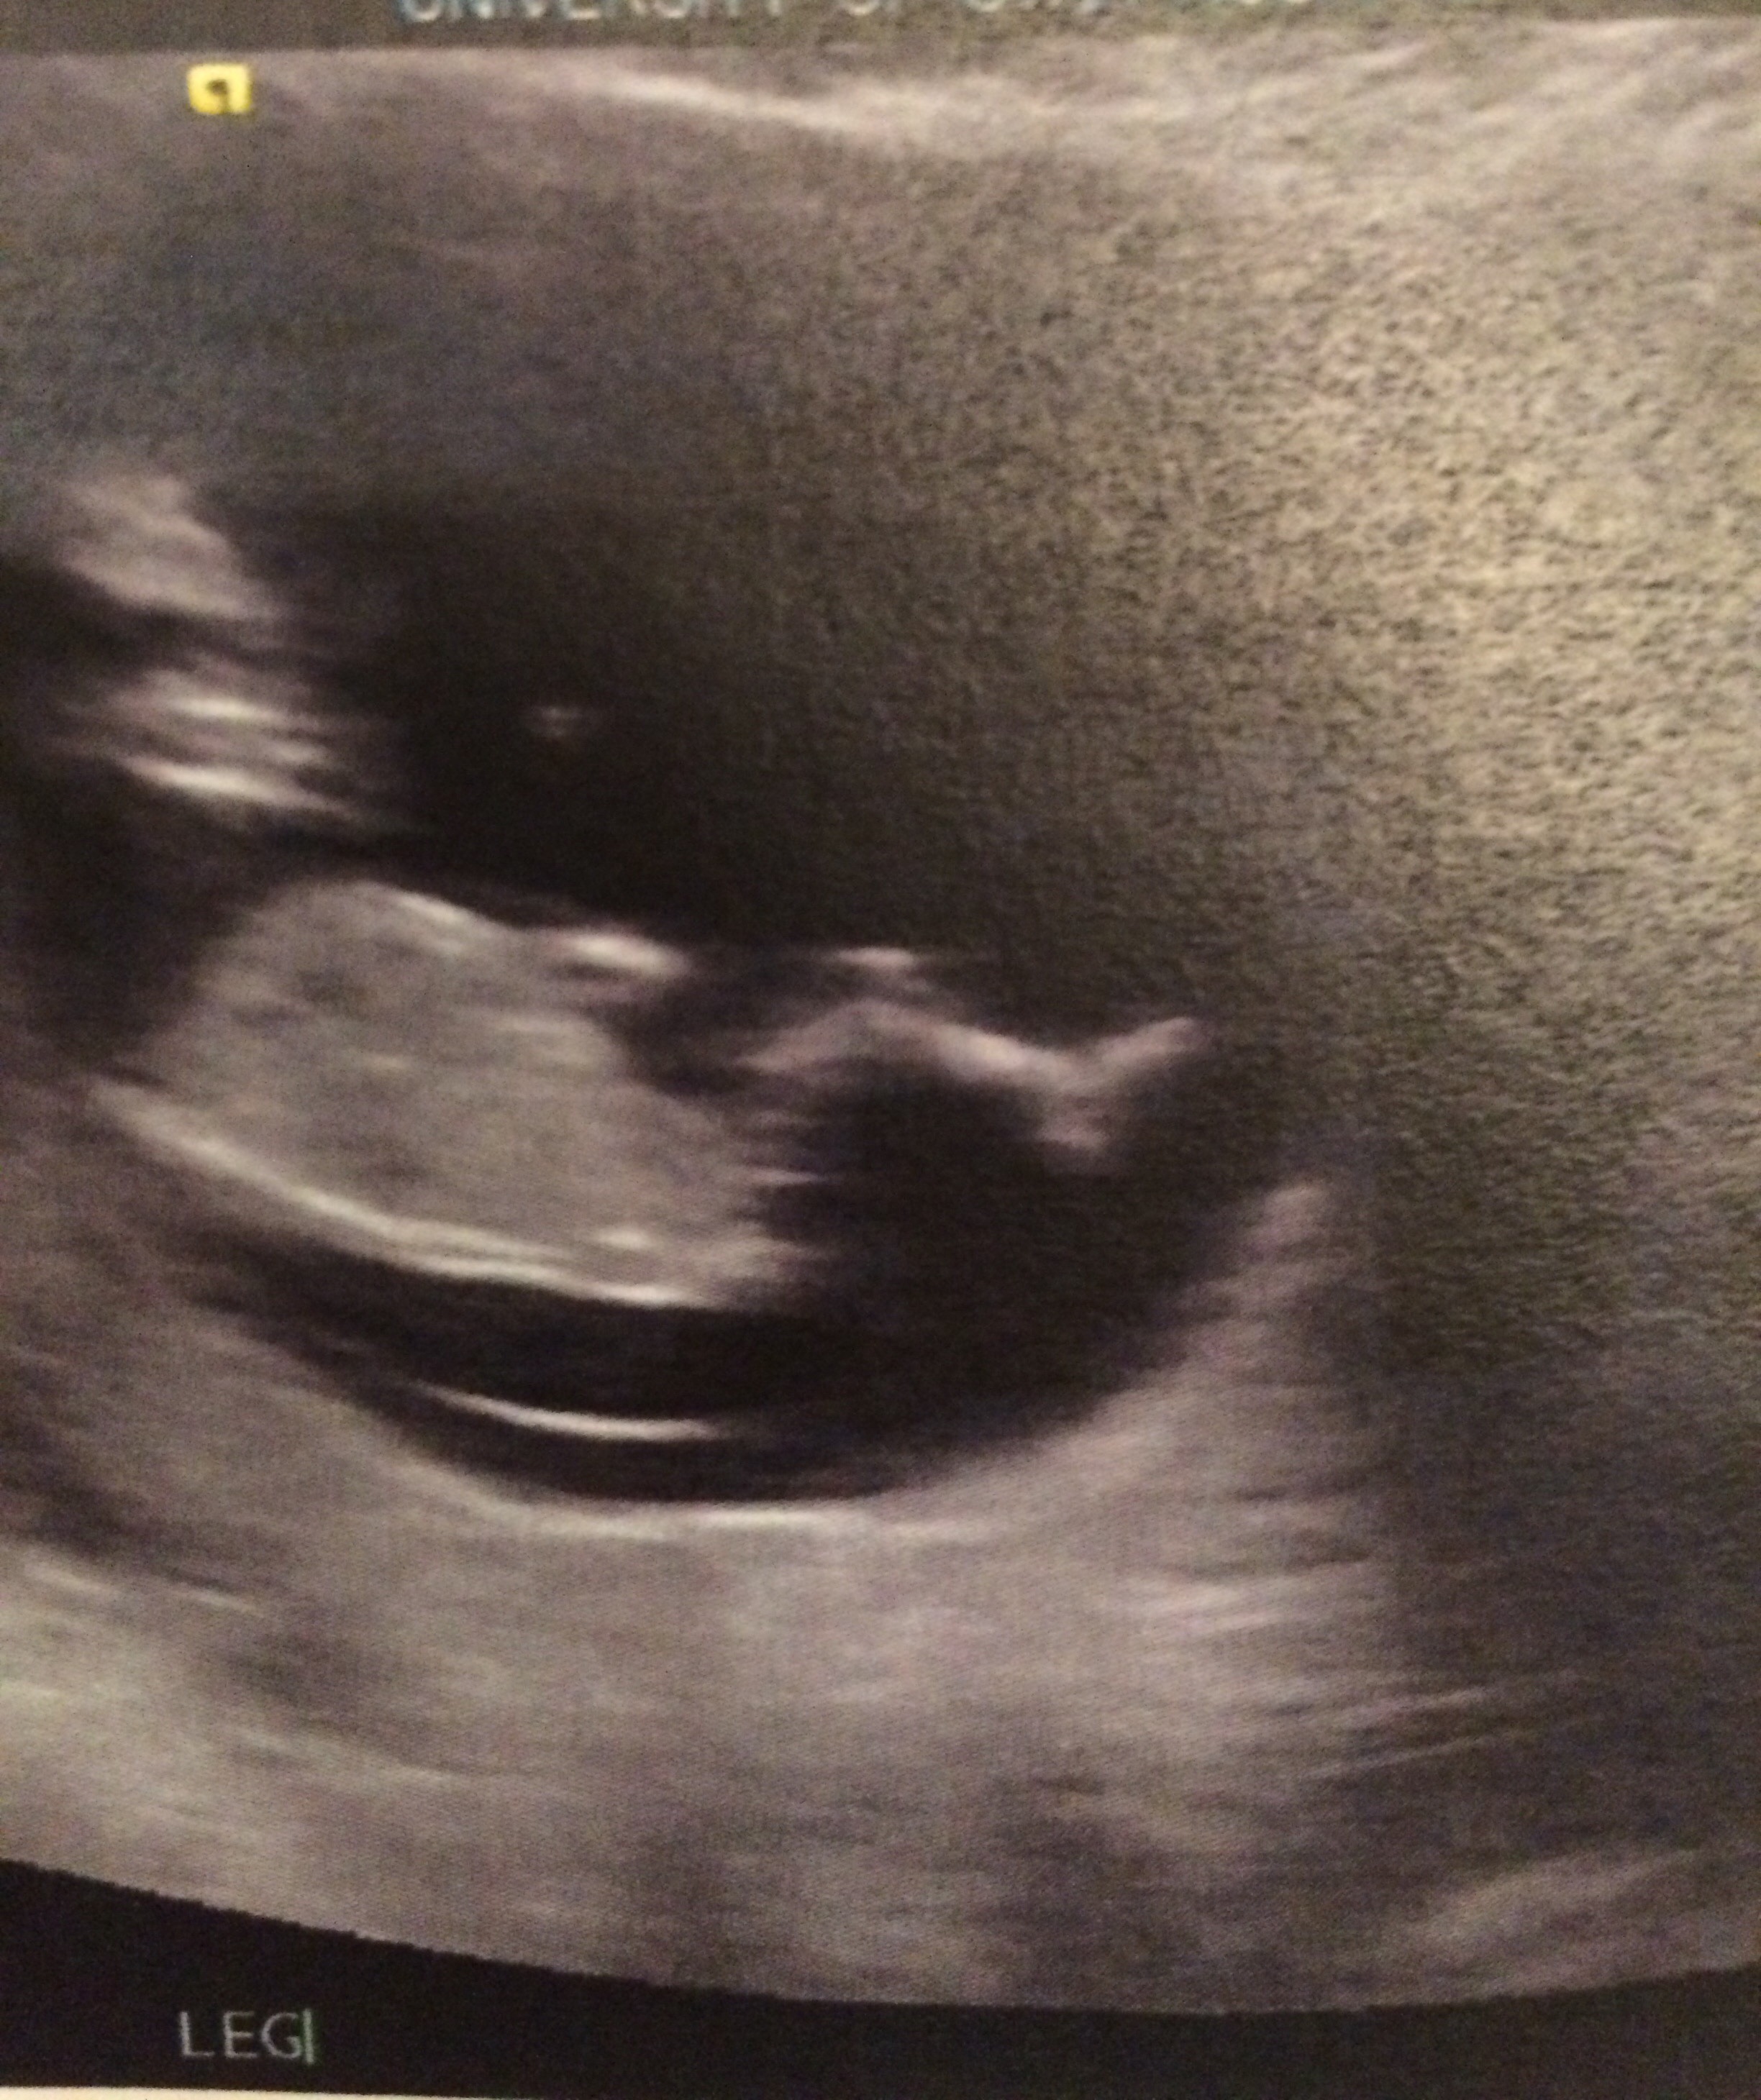

I had an ultrasound this morning because I had been cramping and spotting and the baby looked great!! It was measuring at 12w1d and it was jumping everywhere like a crazy little jelly bean! It had a heartbeat of 169 and it had little legs and arms!!! I've never made it this far in a pregnancy before so I am beyond excited. I could dance (if my nausea would allow it). But I figured I'd make a post so future people who search for spotting or cramping can have a happy story to look at too!

• Thank you everyone! I felt that this was a safe board to share my exciting news on seems how I feel like everyone here has a deeper understanding of how I feel. I keep looking at the pictures and I tear up every time. I'm so excited to hear about everyone's miles stones as they come up! This is such an amazing group of women!